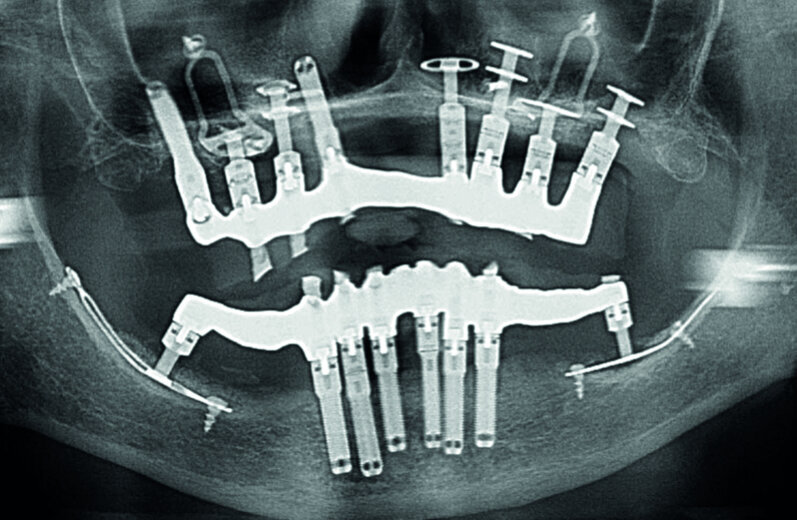

Figs. 8a et b : Contrôles radiologiques du bon ajustement des armatures après vissage.

Pose du bridge :

Après l’essayage en bouche, facilité par la passivité, régler l’occlusion, vérifier l’esthétique et la phonation, puis répartir le vissage manuel (vis or M1.4). Enfin, contrôler radiologiquement le bon ajustage de l’armature (Figs. 8a–b). À 24 h, resserrer manuellement les vis à 10 N/cm, fouler une boulette de téflon dans le puit de chaque vis et le recouvrir à l’aide d’un composite.